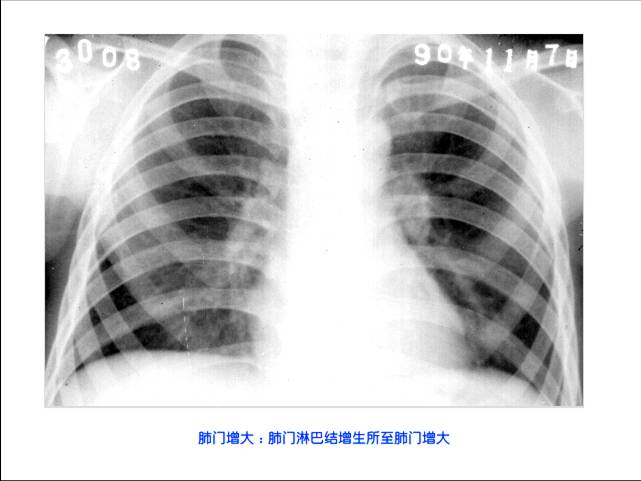

照片名称:肺门增大

肺门淋巴结